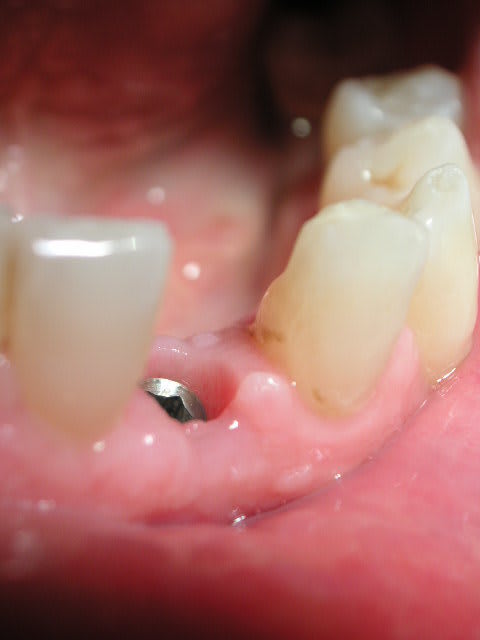

planche 1 : patient adressé par son endodontiste. Ces incisives ont été traitées à plusieurs reprises sans réussite. Grosses pêches apicales + fistules. Le patient est mécontent de la forme du bloc incisif inférieur. Extraction 32-31-41-42 pour raisons endodontiques. Contrairement à certains je n'implante pas dans une zones infectées même après un nettoyage méticuleux du site. Donc GBR avec os autogène + BioOss et BioGide pour préserver tout le joli nonos.

planche 2 : 4 mois après, implantation en 32 et 42. Exercice d'aujourd'hui à 14H00. Mise en place d'un bridge provisoire vissé réalisé au fauteuil.

Voila la suite du cas en question avant prise d'empreinte definitive :